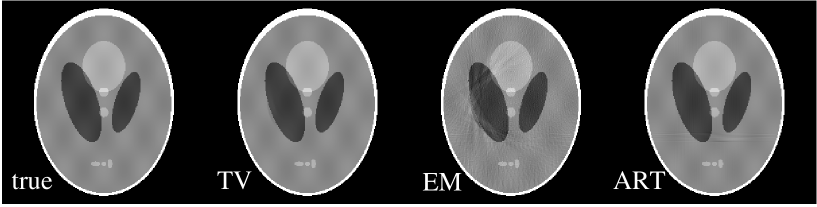

In the first limited-angle problem, we reduce the scanning angular range from 209∘ to 180∘ and generate projection data at 128 uniformly distributed views from the Shepp-Logan phantom. Again, the detector at each view has 512 bins. For this scan, the number of non-zero data points is 52,730 , which is even more than the number of non-zero pixels in the Shepp-Logan phantom itself.

We display in the upper row of Fig. 6 images reconstructed from this set of data by use of the TV, EM, and ART algorithms. The profiles of these images along the central horizontal and vertical rows are displayed in the middle and lower rows. The number of iterations for each of the TV, EM, and ART reconstructions is 1000. The images in row one of Fig. 6 show that the TV reconstruction is virtually indistinguishable from the true phantom and that the images obtained by use of the EM and ART algorithms are also reasonably accurate with only small distortion near the bottom of the images. This distortion of the EM and ART images is understandable because the 180∘ scan covered the top half of the phantom. The high iteration numbers were used for achieving convergence in the bottom half of the image. Additionally, the EM image shows a high frequency artifact not seen in the TV or ART images, because the back-projector in each case is ray-driven, which is known to yield such Moire patterns in EM images De Man and Basu (2004). But, as explained above, we are comparing the reconstruction algorithms on their ability to solve the linear system corresponding to the imaging model, and we therefore use the ray-driven backprojection because it represents exactly the system-matrix adjoint.

We explore further reduction in the scanning angle by taking 64 angular samples uniformly distributed over an angular range of only 90∘, covering the first quadrant of the Shepp-Logan phantom in Fig. 7. We display in row one of Fig. 7 images reconstructed by use of the TV, EM, and ART algorithms. The number of iterations for the TV, EM, and ART reconstructions is 10,000. In this case, there were 26,420 non-zero projection measurements, which would seem to be sufficient for the TV algorithm considering the sparseness of the phantom’s image gradient. But the instability of the corresponding linear system appears to be too strong for accurate image reconstruction as can be seen in the reconstructions shown in the upper row of Fig. 7. In the middle row of Fig. 7, we show the profiles along central lines in the horizontal and vertical directions of the TV image. The corresponding true profiles are also displayed as the thin lines. The TV image contains a deviation from the true phantom on the left-hand edge, which is evident in the shown horizontal profile. On the other hand, the EM and ART reconstructions are highly distorted. We have studied in row three of Fig. 7 the profiles along central lines in the horizontal and vertical directions of the EM and ART images. Distortions in these images are clearly shown in these profile plots. We have also studied the image error as a function of iteration number in an effort to determine whether or not the TV algorithm will converge to the true image. For the previous cases the image error was tending to zero, but for this 90∘ scan the image error appears to converge to a small but finite positive number. The system matrix corresponding to the 90∘ scan appears to violate somewhat the ERP.